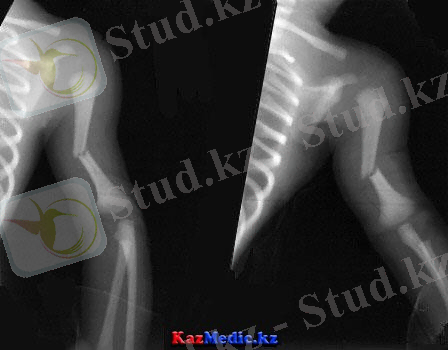

Иық сүйегінің диафизінің сынығы